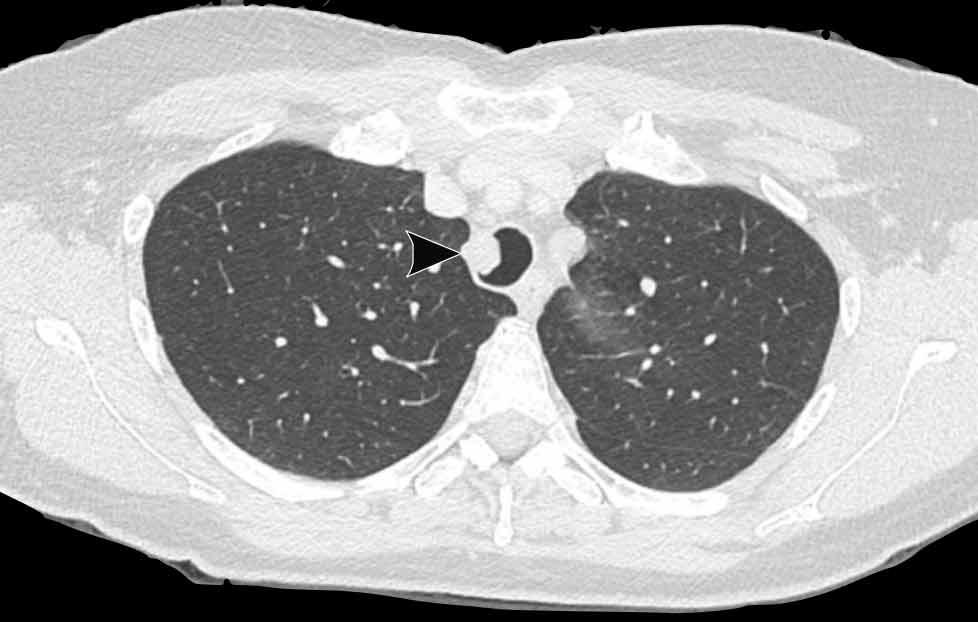

Tiếp tục xem trên cửa sổ phổi…

Hình ảnh cho thấy nhiều tổn thương dạng nang ở cả hai phổi (đầu mũi tên).

Trong một số ít trường hợp, tổn thương có thể lan rộng vào nhu mô phổi, biểu hiện là các nốt dạng nang thường gặp nhất ở các phân thùy đỉnh phụ thuộc trọng lực của thùy dưới. Có một nguy cơ nhỏ về biến đổi ác tính từ u nhú tế bào vảy thành ung thư biểu mô tế bào vảy.